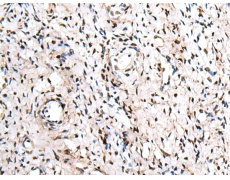

IHC positive control:

Human cervical cancer

IHC Recommend dilution:

25-100